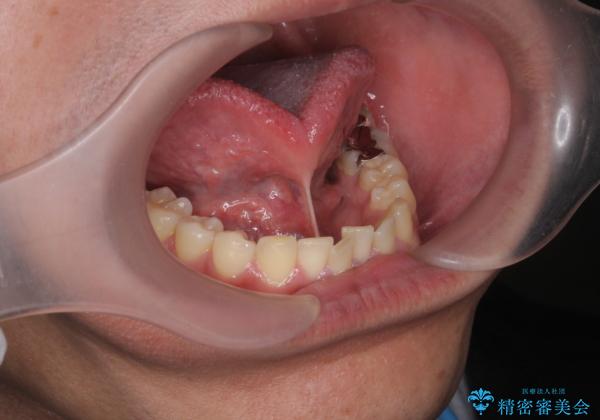

[ 舌小帯の長い付着 ] 舌の動きが悪く話しづらい

- 舌の動きが悪く話しづらい。舌小帯の形成を求めて来院されました。

視診にて長い舌小帯の付着が認められたので、形成術を行います。

術後、舌の動きが良くなり滑舌が良くなったことを実感されていました。